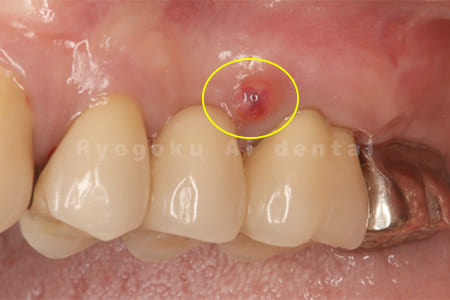

他院で歯根端切除術を行ったが、良くならないとのことで、ご来院された患者様です。再根管治療後、サイナストラクトが消失しなかったため、歯根端切除術を行いました。現在、一年経過しておりますが、再発もせず、経過良好です。